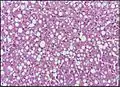

Micrograph of fatty liver showing lipid steatosis. H&E stain. Steatosis with a centrilobular pattern, which is the general tendency for steatosis in adults.[11]

Steatosis with a centrilobular pattern, which is the general tendency for steatosis in adults.[11]